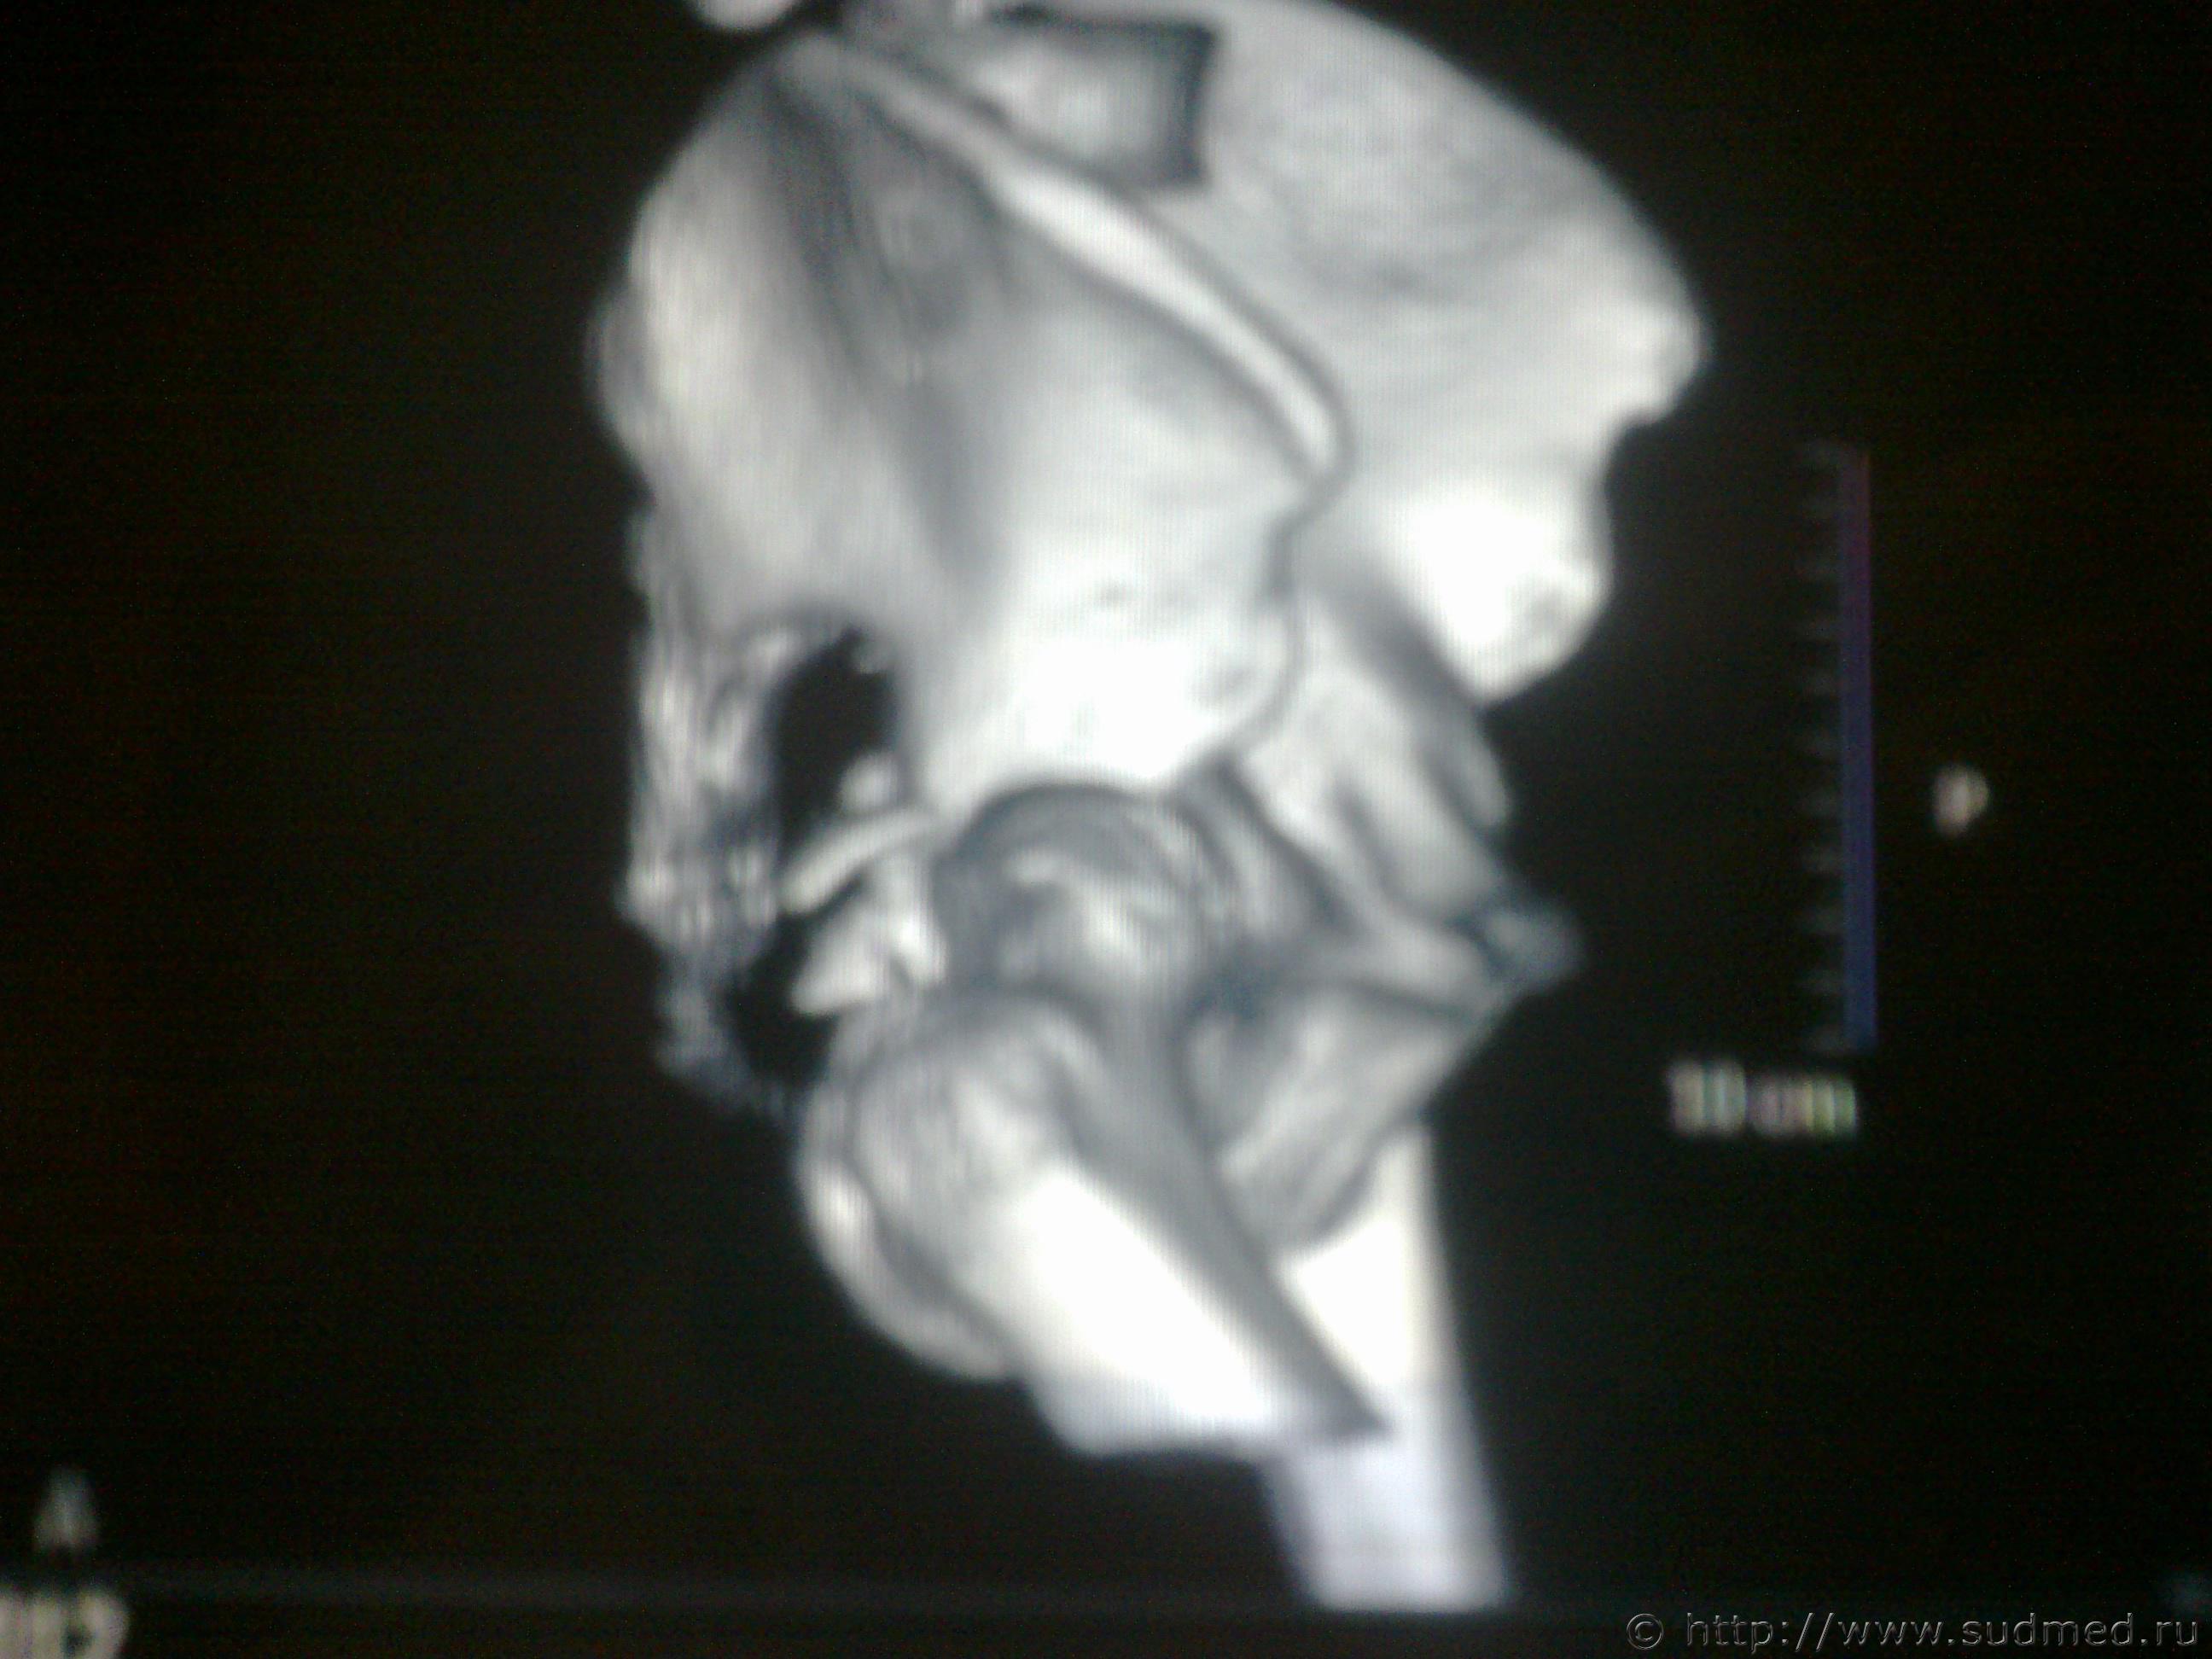

На основании этих снимков можно сделать заключение о вреде здоровья?

Эскизы прикрепленных изображений

Судебная медицина - Прикрепленное изображение Судебная медицина - Прикрепленное изображение

1. Вертлужная впадина сломана - факт.

2. Костные отломки ее несколько смещены .

Следовательно - тяжкий вред (пункт 6.11.4. )

Совсем другое дело.

Видно хорошо.

Смещение отломков в области вертлужной впадины несомненное. Видно хорошо. Тяжкий вред. Без вариантов.